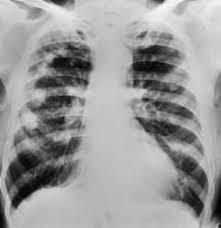

lung - pleural effusions, interstitial fibrosis or pulmonary nodules

Caplan’s syndrome

rheumatoid arthritis and pneumoconiosis

combination of inhaled dust and disturbed immunity of RA that manifests as intrapulmonary nodules

occurs particularly in coal worker’s pneumoconiosis